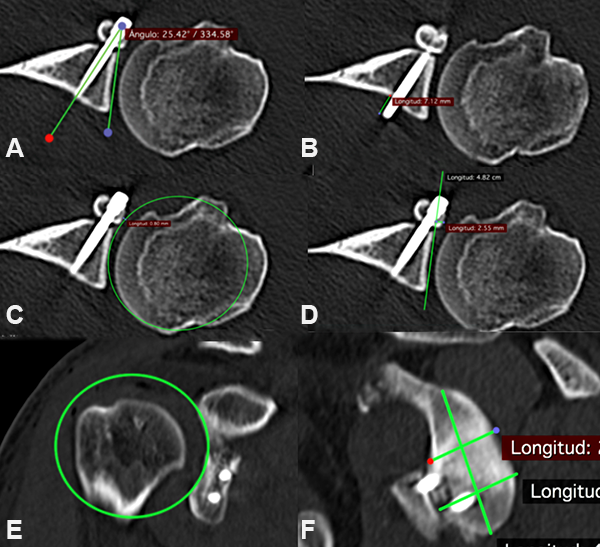

En el post operatorio se realizó un estudio imagenológico 24 horas luego de la cirugía, con TC con reconstrucción 3D. Para la medición de variables radiológicas se utilizó el programa Osirix Lite® versión 10.0.1 para Mac, todas las imágenes fueron analizadas por un mismo evaluador, diferente al cirujano y se analizaron las siguientes variables, descritas por Kany et al.:12 el ángulo tornillo – superficie articular, el largo del tornillo superior en corte axial, distancia entre superficie articular e injerto (con método de tangente y círculo) en los cortes axial y coronal y la relación injerto – glenoides, dividida en cuartos en el corte sagital (fig. 3).

Figura 3: Índices Evaluados. A) Ángulo tornillo-articular. B) Largo tornillo superior. C) Distancia Injerto – Articular método círculo (axial). D) Distancia Injerto – Articular método tanjente (axial). E) Distancia Injerto – Articular método círculo (Coronal). F) Relación Injerto- Glenoides (sagital).

El ángulo tornillo-articular promedio fue de 32, 9°. En la medición del largo del tornillo superior sólo un 6% fue mayor a 4 mm. Con respecto a la distancia injerto - articular con método tangente en corte axial fue de +1 (+2,5 – 0) y la distancia injerto - articular con método circular axial y coronal fue de 0 (+2 – -1) y 0 (+2,5 – 0) respectivamente. En todos los pacientes se obtuvo una posición subecuatorial en la relación injerto – glena evaluada por cuartos en corte sagital. Así mismo, en todos los pacientes se obtuvo una posición “flush” del injerto (fig. 4).